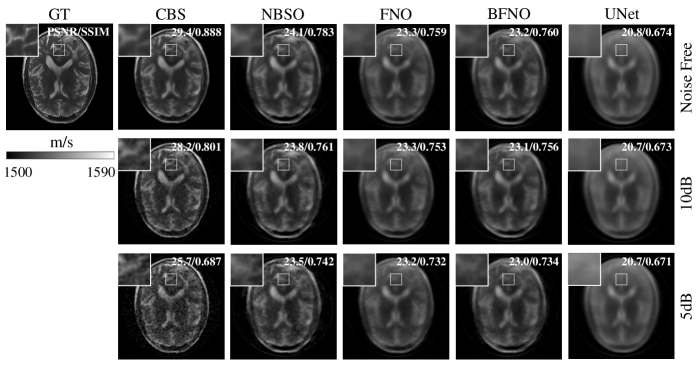

9.2 USCT FWI for Brain Phantoms

Table. 6 showcases the USCT FWI’s performance on 30 brain phantoms using NBSO, FNO, UNet, BFNO, and CBS solvers at different SNR levels (noise-free, 10dB, 5dB) for observed data. NBSO consistently outperforms all neural network-based methods in reconstruction quality, regardless of noise levels. This is further illustrated in Fig. 8, where we display the reconstruction results for a brain phantom.

SNR Metrics CBS NBSO FNO BFNO UNet

Clean PSNR 28.3 23.8 23.0 22.6 21.0

SSIM 0.883 0.783 0.765 0.760 0.711

10dB PSNR 27.5 23.5 22.9 22.5 21.0

SSIM 0.818 0.762 0.757 0.758 0.709

5dB PSNR 25.7 23.1 22.7 22.4 20.9

SSIM 0.685 0.738 0.734 0.733 0.706

Table 6: Comparison of FWI reconstruction quality across 30 brain phantoms. Each row indicates the reconstruction PSNR & SSIM at a specific SNR level, and each column corresponds to a different neural network architecture. NBSO consistently exhibits superior reconstruction quality compared to other neural networks.

Refer to caption

Figure 8: USCT FWI reconstruction of brains using CBS, NBSO, FNO, BFNO, and UNet. Results of three SNR levels (Noise-Free, 10dB, 5dB) are reported. 256 transducers are involved for emitting and receiving. NBSO consistently outperforms other neural network-based methods in reconstruction quality.